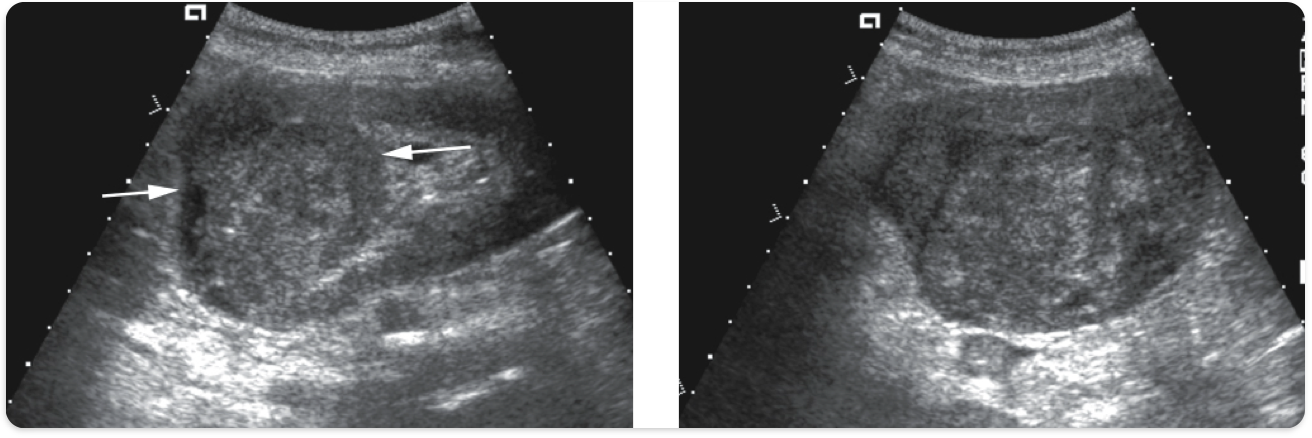

Simple renal cyst. Anechoic, smooth walls, posterior enhancement.

Complex renal cyst. septations, debris, irregular borders, papillary projections.